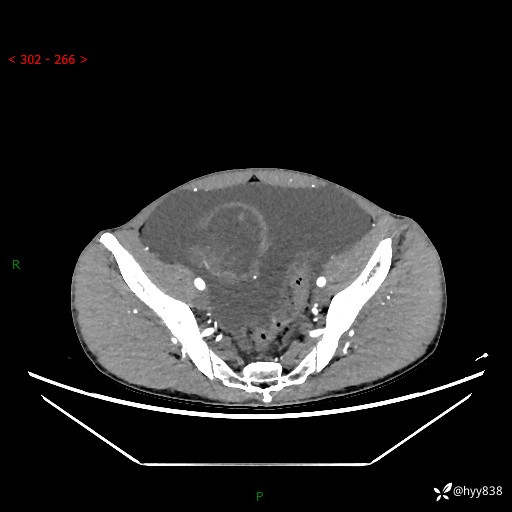

现病史:患者10天前无明显诱因出现腹部胀痛不适,无畏寒发热,无胸痛胸闷,无心慌气短,无恶心呕吐,无腹泻及黑便,无粘液血便及里急后重等症状,4天前在当地县人民医院就诊,行腹部CT示:下腹部占位性病变,腹腔及盆腔积液;今患者为求进一步诊治来我院治疗,门诊以“腹水”收治入院。 发病以来,精神饮食可,大小便正常,体重体力无明显变化。

腹部CT平扫+增强